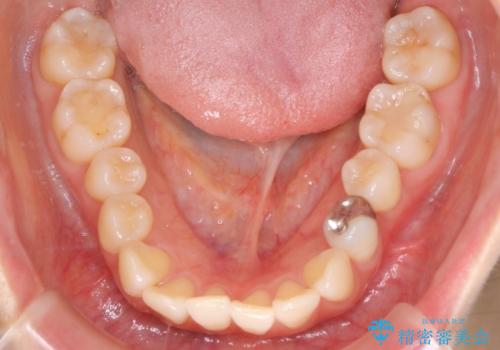

【インビザライン】かみ合わせを整えたい

- インビザラインで非抜歯治療を行いました。IPRと拡大をし、叢生、咬合をきれいにしました。

主訴であったかみ合わせを正しい位置に動かし、バランスよくかめるようになりました。矯正治療終了後にメタルインレーをセラミックインレーに替えました。